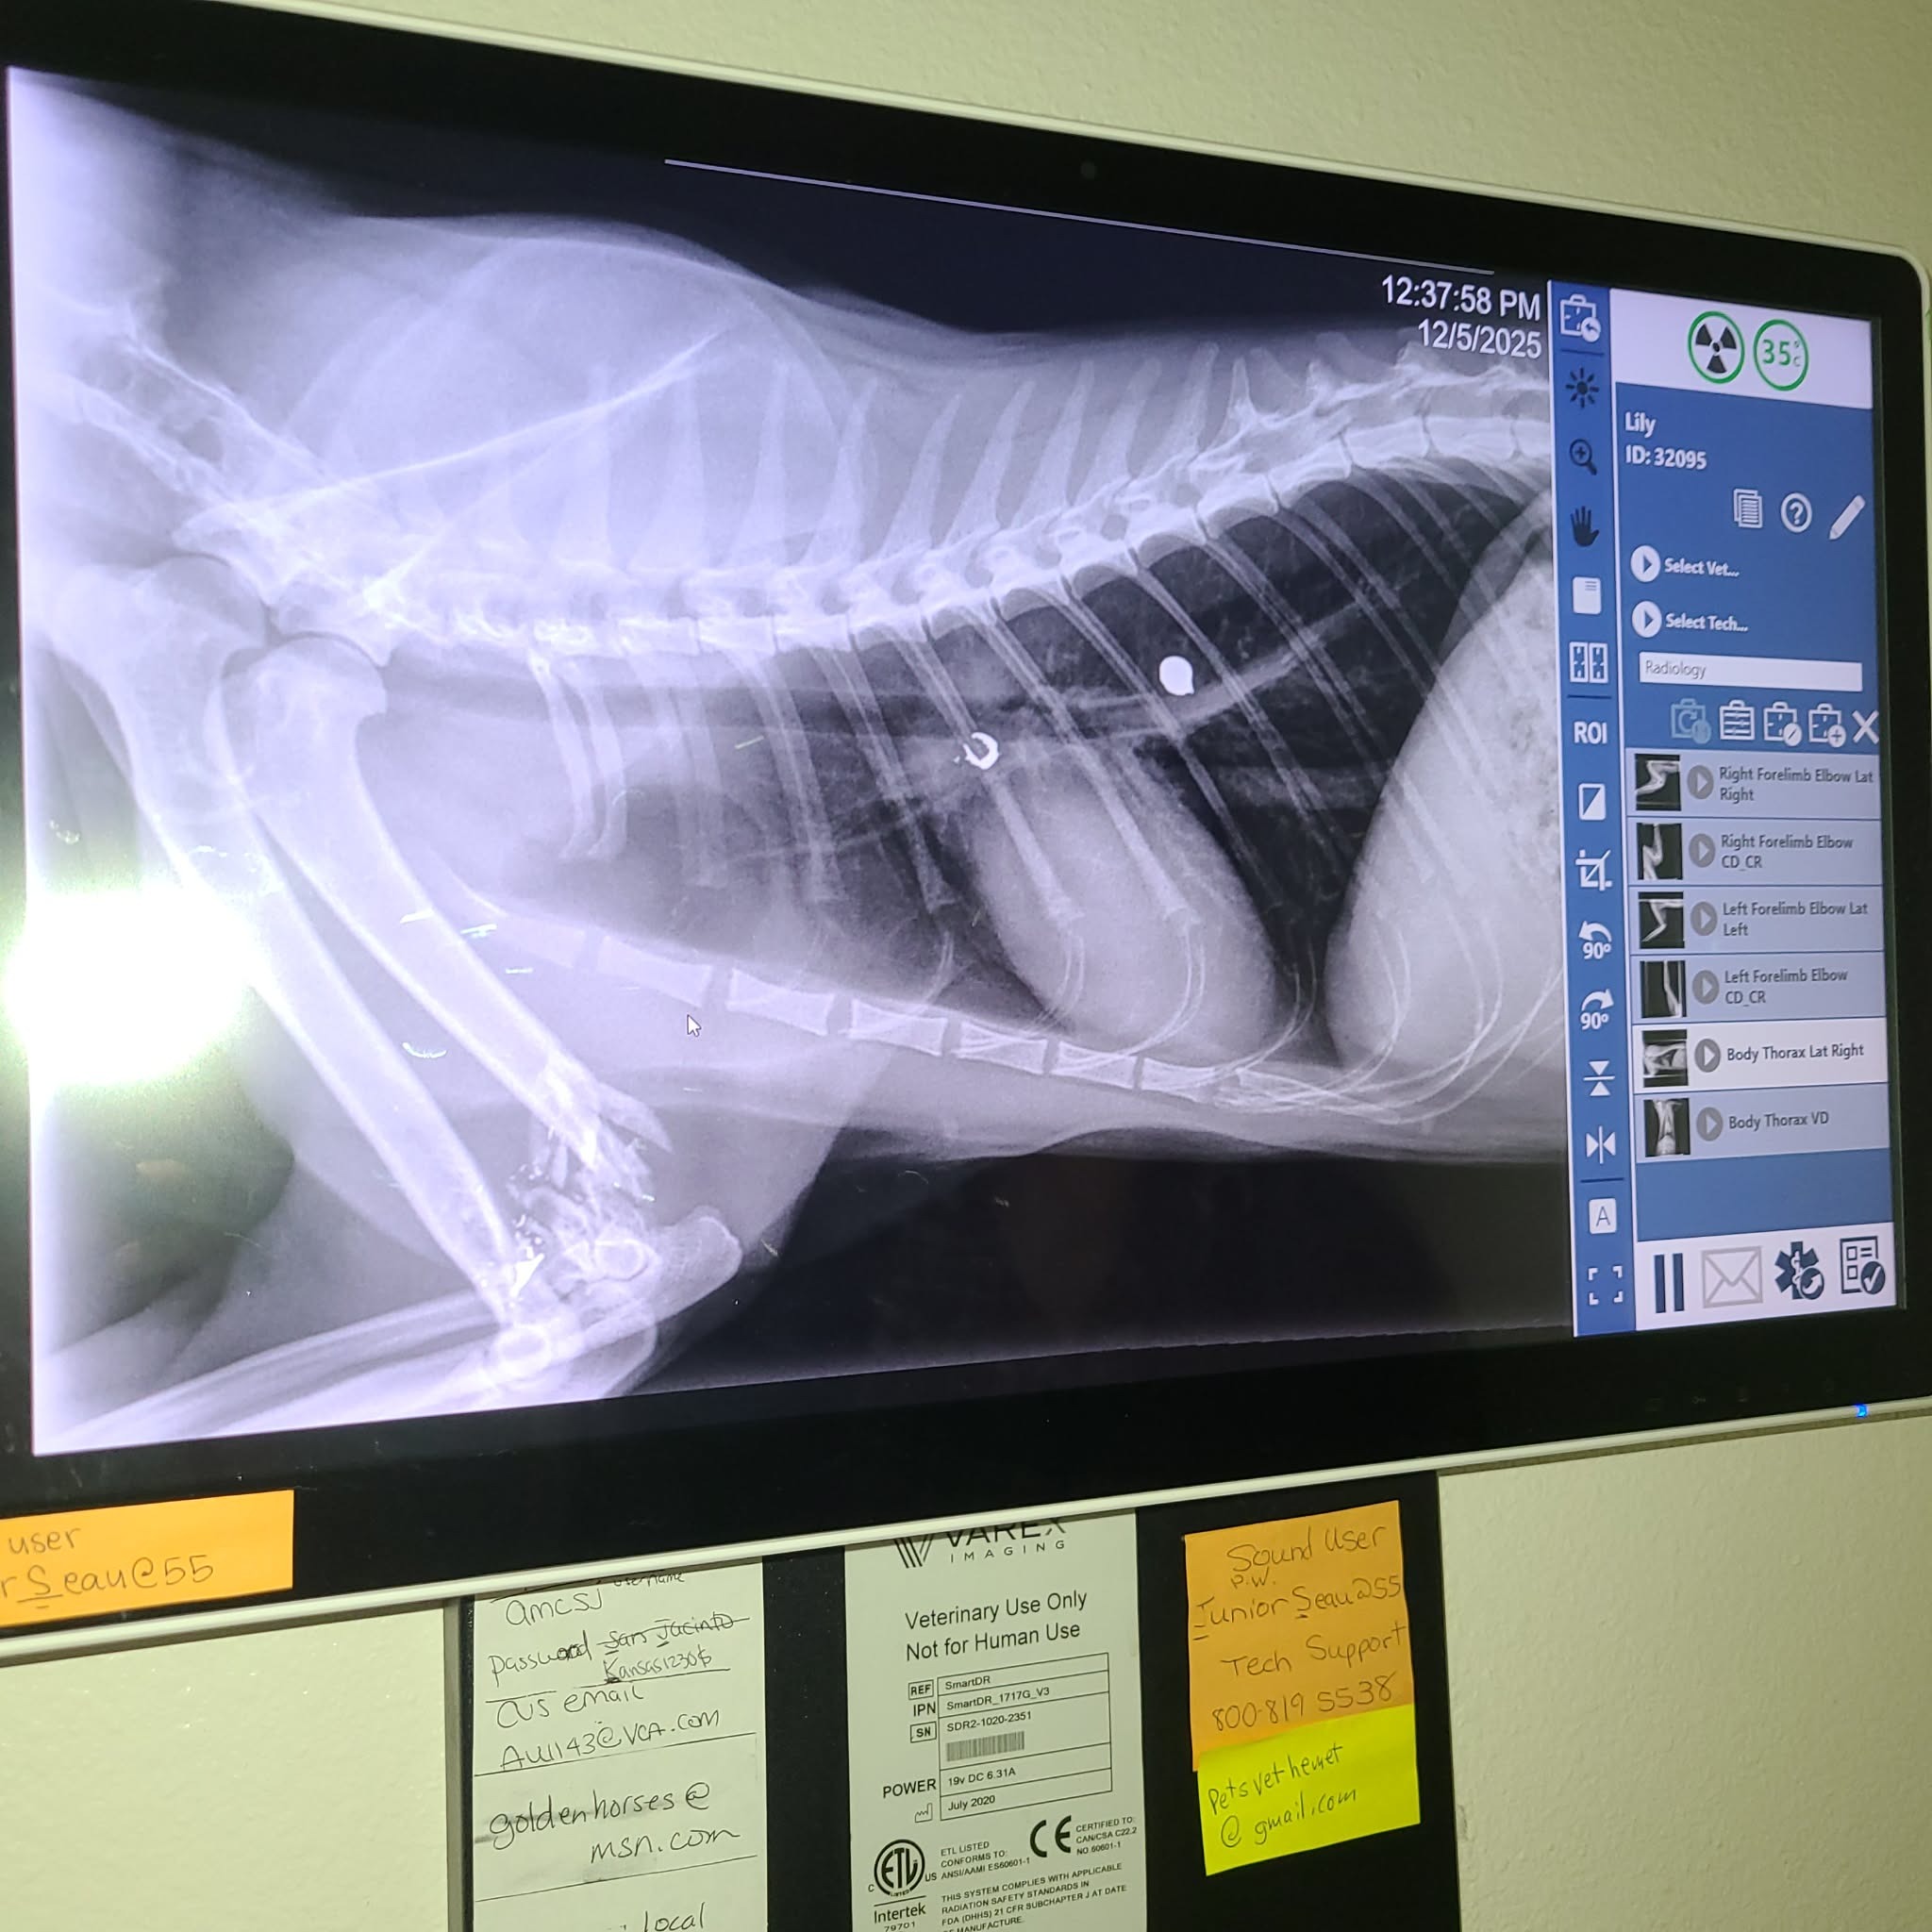

On Friday, our sweet neighborhood stray cat Lily endured something no animal should ever face. A terribly cruel person shot her (with a G*N), injuring her front leg and sending shrapnel into her chest. Lily has always been a gentle presence in our neighborhood: a caring mother, a friendly companion, and our unofficial mouse catcher. She did not deserve this.

Despite her injuries, Lily is a survivor. She has stayed strong, and today, Monday December 8, she is undergoing surgery to fully amputate her damaged leg. This surgery is her best chance at a pain free, healthy life.